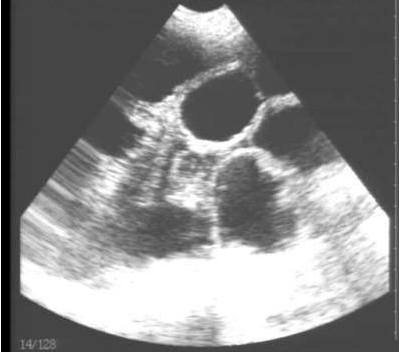

豬用B超機檢測有胎兒圖像

需要注意的是,出現云團狀必須雙側檢查加以確認.根據B超機顯示圖我們大致可以判斷孕齡.圖像呈橢圓或者卵圓形大致為30天左右孕齡;圖像呈橢圓形或者卵圓形外,有明顯發亮骨骼圖像大致為50孕齡左右;圖像囊胚消失,發亮處隱約可見竹節狀東西為成型胎兒骨骼,一般為后期80孕齡以后。一般B超機成像會出現三種顏色,白色、黑色、灰色。白色為密度較高的物體,如骨骼或者結實.黑色一般為液體,包括血液、羊水、組織間隙液體、炎癥病灶等。灰色一般為實質性物質,如肌肉。